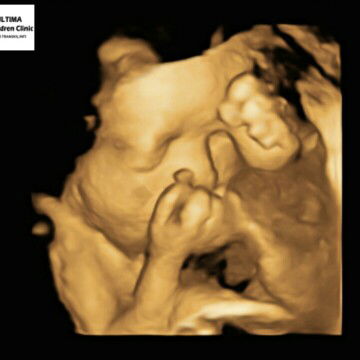

Menantikan saat menjadi ibu

babyq kayaknya pemalu.

Tiap usg nutupi wajahnya klo gak mulutnya, dg gaya gemesnya. Apalagi klo ayahnya nyentuh perut debay nya diem giliran gk disentuh ayahnya kruntelan sama bunda.